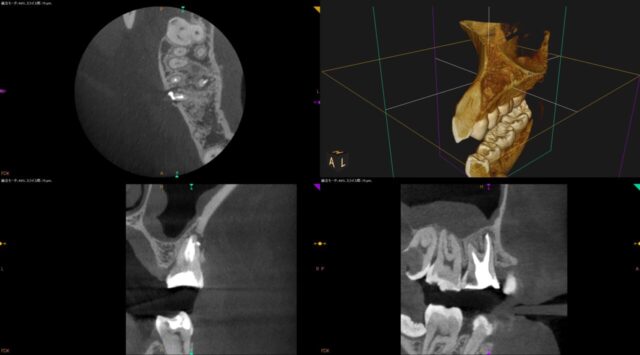

| 注意点 | この根管には偽根管と本来の根管とは違う、人為的な偽の根管が存在。本来の根管の中の感染源を除去するのが困難な症例。ニッケルチタンファイルを使用しプレカーブを付与して本来の根管へアプローチ。この歯は以前根管治療がされている。しかし近心形態が複雑で未治療根管が存在。MB2が存在。またCTを見たら側枝も存在。 |

| 備考 | 本症例は歯を抜かずマイクロスコープを使った根管治療根の治療で歯を抜かず残した。↓以下に治療動画を載せる。CT像を確認したら非常に根管形態が複雑であった。MB1、MB2<側枝が存在。マイクロスコープとCTがないと戦えない。根管治療は一回で終了。仮歯で経過観察。 |

治療前

治療後